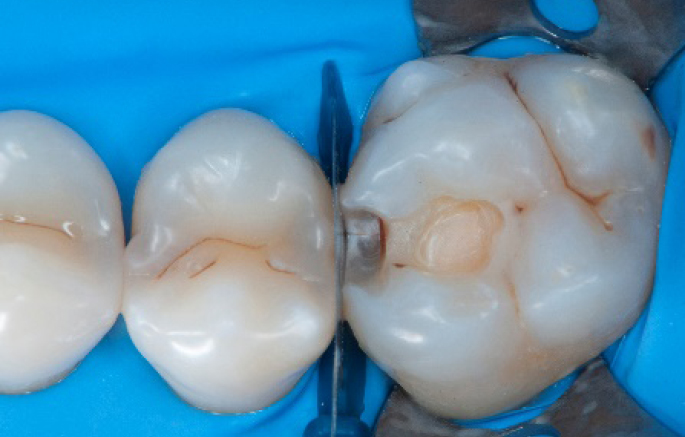

Step 5:

Buccal view of the Palodent1 system.

Step 6:

Selective enamel etching procedure with Conditioner2.

Step 7:

Adhesive application with a universal adhesive, Prime&Bond3.

Step 8:

Transformation of class II into class I, restoring the interproximal wall with Spectra ST4 composite in shade A2.